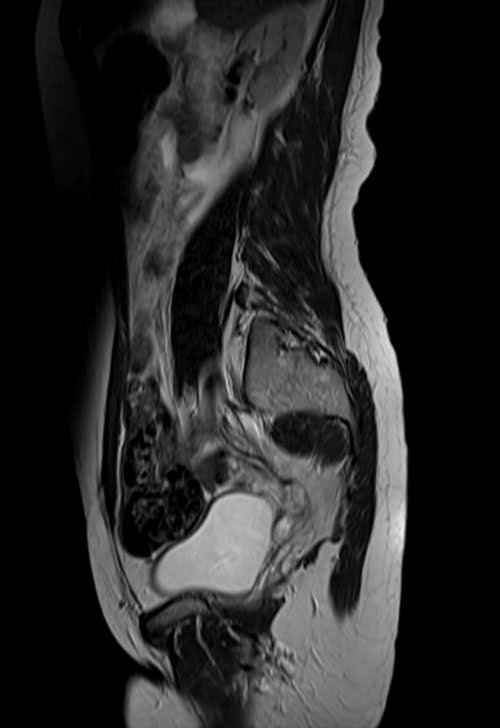

mri lumbosacral plexus sagittal t2 image 1 - MRI